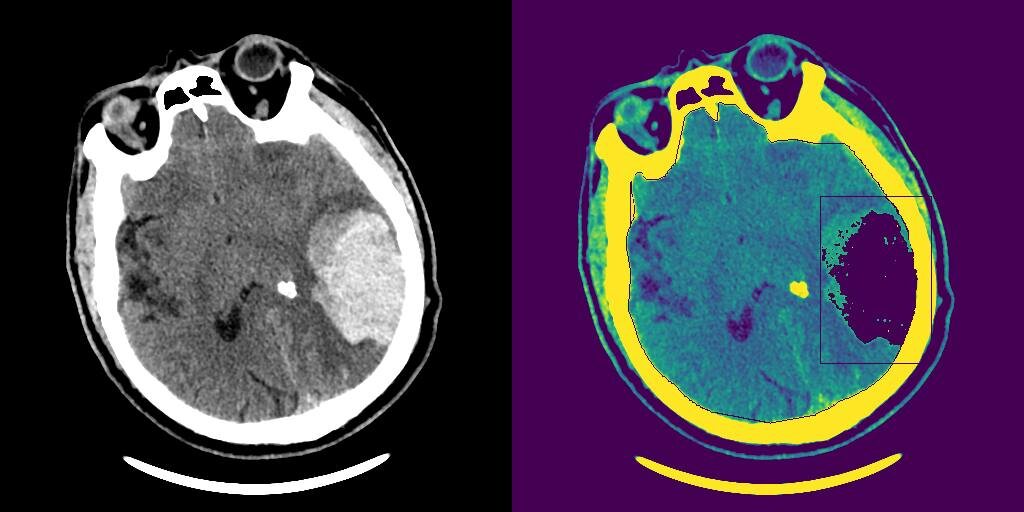

Новая ИИ-система будет сопоставлять данные мультиспиральной компьютерной томографии головного мозга с цифровыми маркерами, указывающими на риск критического ухудшения состояния пострадавших. Это позволит медикам быстрее и точнее оценивать тяжесть травмы и выбирать тактику лечения.

Как сообщил нейрохирург НОКБ имени Н.А. Семашко Артём Копылов, на сегодняшний день уже создан алгоритм анализа МСКТ-изображений и обучения на их основе моделей искусственного интеллекта. Система позволяет с высокой точностью определять объём сложных внутричерепных гематом и локализацию повреждений.